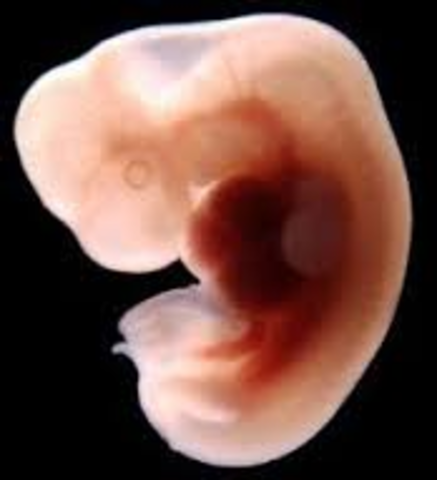

• Week Five: The embryonic stage begins

Week Five: The embryonic stage begins

• Week Six: The heart begins to beat

Week Six: The heart begins to beat

Its at the size of about a peanut but not fully developed. The heart is now starting to form.

• Week Seven: Arms and legs begin to grow

Week Seven: Arms and legs begin to grow

The heart beat is in one chamber. The arms and leg buds start to grow.